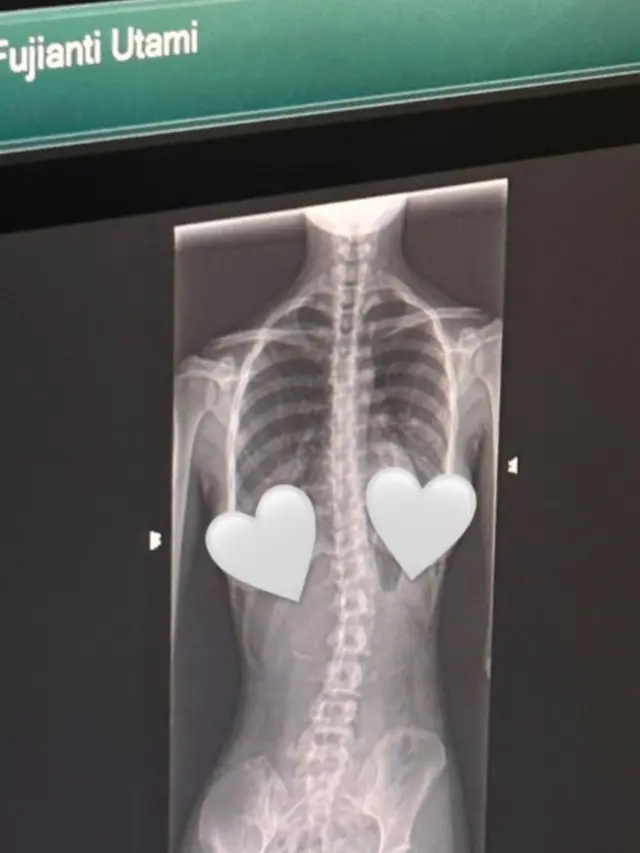

Fimela.com, Jakarta Kabar kurang mengenakan datang dari Fujianti Utami Putri alias Fuji. Secara mengejutkan, lewat postingan Instagram terbarunya, pemeran “Bukan Cinderella” itu umumkan kalau dirinya idap skoliosis.

Di Instagramnya, Fuji memperlihatkan 3 slide foto. Salah-satunya memperlihatkan hasil rontgen tulang belakangnya yang bengkok ke kiri.

Skoliosis merupakan kondisi tulang belakang melengkung atau menyamping secara tidak normal yang ditandai dengan bentuk punggung melengkungs eperti huruf C atau S.